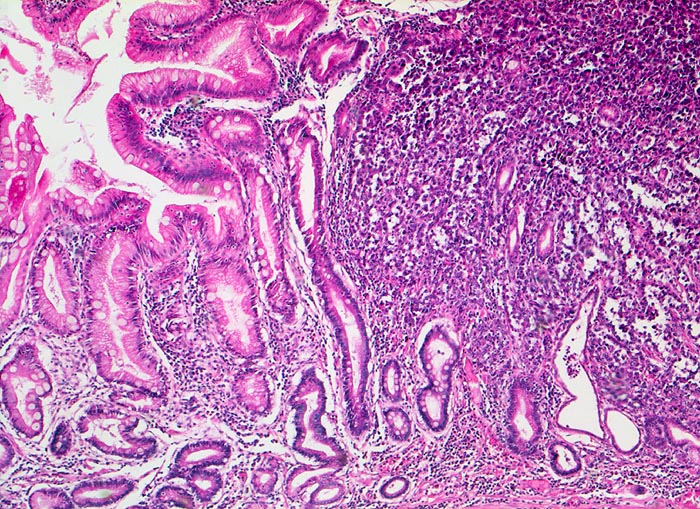

Bei Magenfrühkarzinomen findet sich häufiger ein intestinaler als ein diffuser Typ nach Lauren (Magenkarzinom vom diffusen Typ siehe Differentialdiagnose). Beim intestinalen Typ ist das Tumorgewebe relativ scharf gegenüber der Umgebung abgegrenzt und zeigt meist tubuläre Tumorformationen, die von Zylinderepithel ausgekleidet werden. In der Nachbarschaft von Magenkarzinomen des intestinalen Typs finden sich gehäuft Dysplasien als sogenannte Ausläuferläsionen oder schwere Formen der chronisch atrophen Gastritis mit intestinaler Metaplasie ( 1302).

Am unteren Ende des Präparates Antrummukosa mit mässiggradiger chronischer, geringgradig aktiver Gastritis und ausgedehnter intestinaler Metaplasie (Becherzellen).

Weiter oben Invasion der Magenschleimhaut durch ein teils solides, teils drüsenbildendes Adenokarzinom mit stark atypischen Tumorzellen.